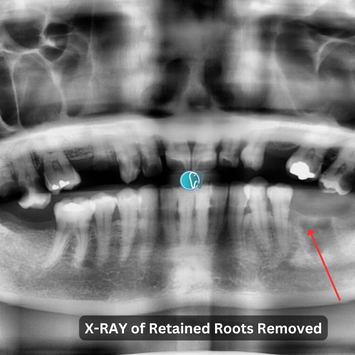

Surgical Removal of Retained Roots #36

Tooth #36 has very tender-to-pressure (TTP) roots, with swelling around the retained roots. Mobility and probing depth are within normal limits. Caries extend to the pulp and are gross and extensive, reaching the crestal level. Sound bone level observed.

Pre-op CBCT taken.

Post-op CBCT taken, showing no remnants. Inferior dental nerve (IDN) and adjacent teeth not involved.